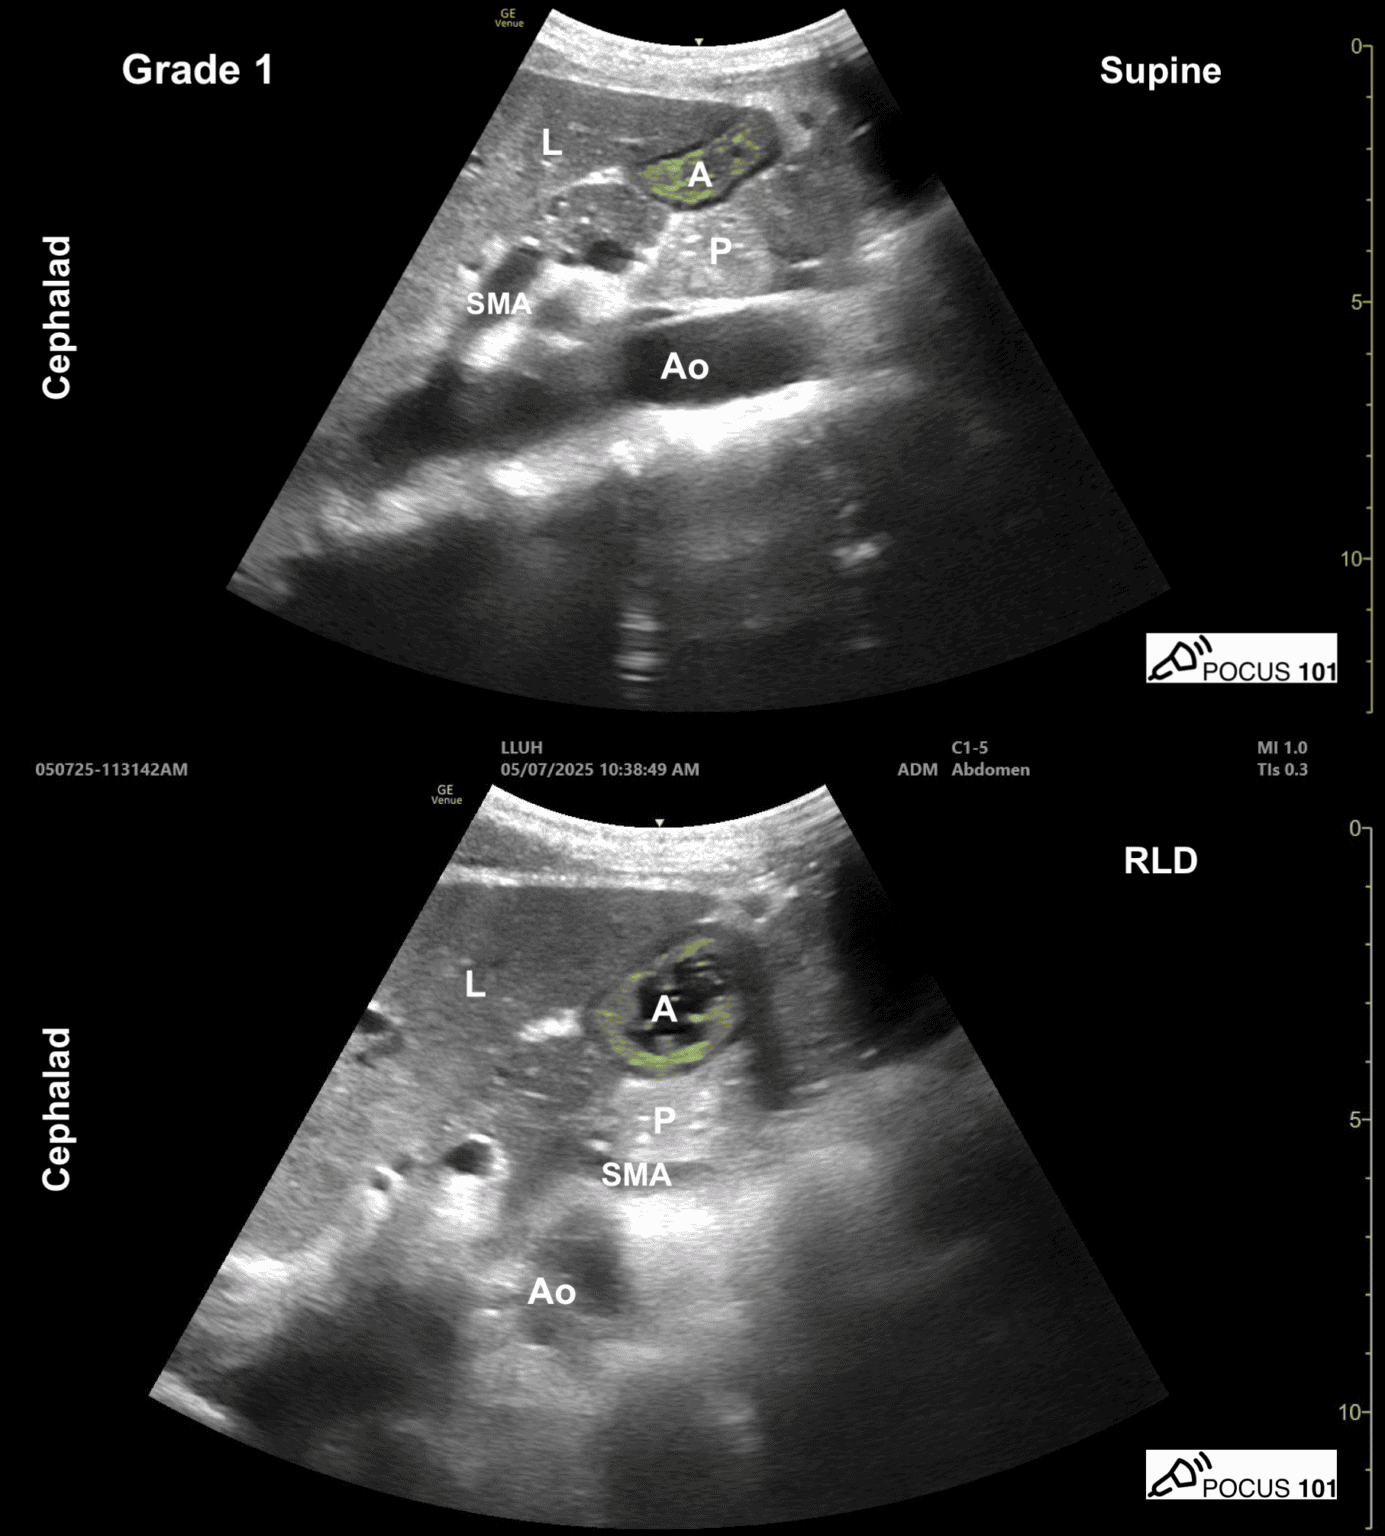

- Lagerung: (1) Rückenlage, (2) Rechtsseitenlage

- Standardschnitt: Linker Leberlappen, Magenantrum, Pankreas, AMS, Aorta abdominalis

- 0: Magenantrum leer in Rückenlage und Rechtsseitenlage

- 1: Flüssigkeit nur in Rechtsseitenlage (baseline Magensekretionen, auch bei Nüchternheit, siehe Bild)

- 2: Flüssigkeit im Antrum in Rückenlage und Rechtsseitenlage